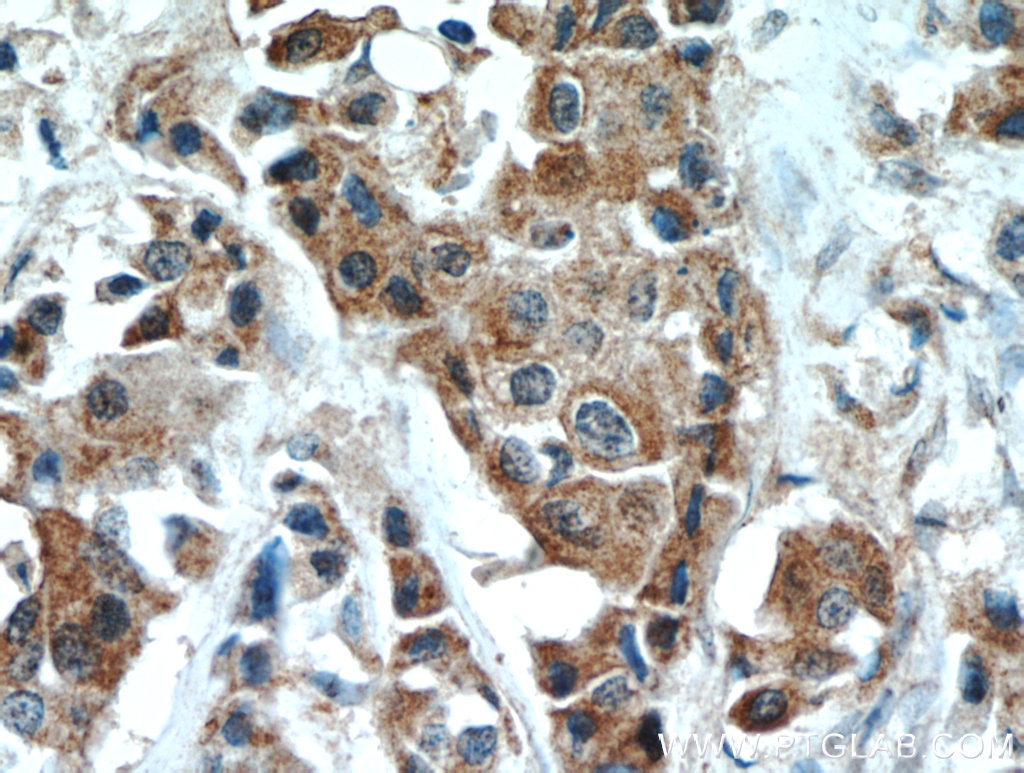

| Positive IHC detected in | human pancreas cancer tissue, human breast cancer tissue Note: suggested antigen retrieval with TE buffer pH 9.0; (*) Alternatively, antigen retrieval may be performed with citrate buffer pH 6.0 |

10636-1-AP targets DLK1 in WB, IHC, IF, ELISA applications and shows reactivity with human, mouse, rat samples.

| 经测试应用 | WB, IHC, ELISA Application Description |